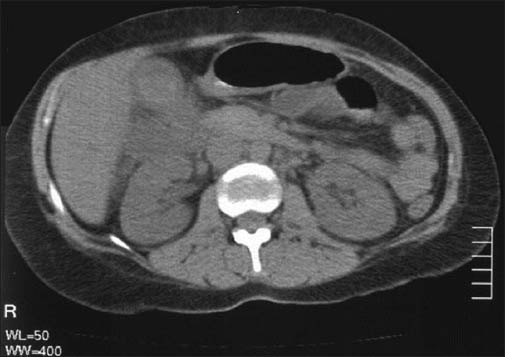

A Man With Abdominal Pain And Acute Renal Failure

A Man With Abdominal Pain and Acute Renal Failure Faisal The patient responded to L normal saline fluid resuscitation to 110/60 mm Hg admitted to a telemetry floor. Initial studies included an abdominal ultrasound which showed hypoechoic masses in the left lobe of the liver without ... Get Content Here